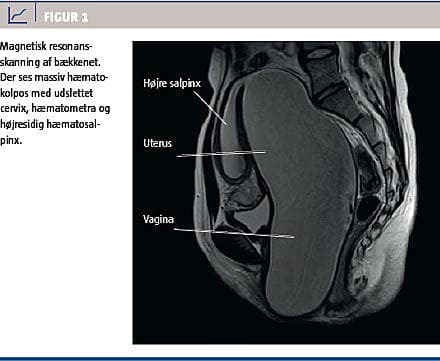

Patienten fik den efterfølgende dag foretaget en magnetisk resonans-skanning, der viste ophobning af menstruationsblod i vagina, uterus og højre salpinx (Figur 1). Senere samme dag fik hun foretaget hymenektomi med udtømning af ca. 800 ml brunligt, gammelt blod. Efterforløbet var ukompliceret, og patienten blev udskrevet dagen efter.

Langt de fleste tilfælde af HI opdages først i teenageårene. Pga. det lukkede afløb fra vagina vil menstruationsmateriale ophobe sig i første omgang i vagina (hæmatokolpos), derefter i uterus (hæmatometra) og salpinges (hæmatosalpinges) og til sidst som retrograd menstruation (hæmatoperitoneum), som i værste fald kan give endometriose [3].